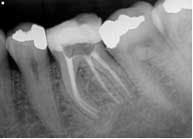

Clinical evaluation revealed no intraoral or extraoral swelling and a large composite restoration in tooth No. 19. Endodontic testing revealed severe pain to cold in tooth No. 19; all other tests were within normal limits (WNL). All other teeth in the quadrant tested WNL. The diagnosis was irreversible pulpitis with normal apical tissue. Radiographic exam revealed a large composite restoration and abnormal anatomy suggesting radix entomolaris. Radix entomolaris is a supernumerary root located distolingually in mandibular molars. The supernumerary root can also be found mesiobucally, and this is called radix paramolaris. The prevalence of a supernumerary root in mandibular molars has been found to be between 2.2% (Skidmore) and 21.5% (Yew and Chan). It is important to carefully study our preoperative and working radiographs in order to recognize the presence and location of abnormal anatomy.

The patient was given treatment options and informed consent, and elected to begin treatment immediately. Profound anesthesia was achieved using two carpules of 2% lidocaine for IANB and one carpule of Septocaine for long buccal infiltration. The tooth was isolated with a rubber dam and accessed under Global operating microscope using round burs and an Endo-Z bur. The distal canal was located in its typical orientation, centered buccolingually between the mesial canals. However, the canal leading to the radix entomolaris was found far to the lingual and off-center. Working length was determined using Root ZX II electronic apex locator. ISO size 6, 8, and 10 files were used to create initial glide path. Instrumentation was completed using ProGlider files to establish glide path, and a combination between Protaper and Vortex Blue files with full-strength sodium hypochlorite irrigation. QMix was placed into the canals after irrigation and agitated with EndoActivator to remove the smear layer and for its antibacterial properties. The canals were filled using warm vertical condensation with System B and Calamus backfill. The patient was given a six-month follow-up appointment and ibuprofen 600 mg for postoperative discomfort.